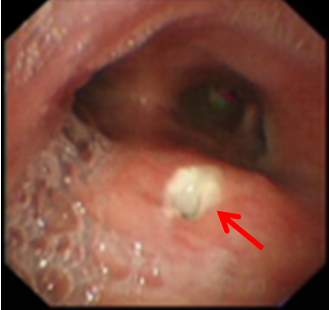

一名60岁男性患者,今年9月底因“咳嗽、咳痰10天”入住我院,1年前在外院确诊食管恶性肿瘤(中分化鳞癌),行放化疗,胸部增强CT显示:胸上段食管癌并食管-气管瘘,右肺及左肺下叶炎症(图1)。(2022-09-26)支气管镜(图2):距离隆突约3.0cm处可见一类圆形瘘口,有黄脓痰粘附,予吸净分泌物后见瘘口处粘膜充血、水肿、溃烂,直径约4mm,4.2 mm外径的电子支气管镜不能通过。(2022-10-17)支气管镜(图3)显示瘘口周围有新生物,活检病理证实为鳞癌。

图2:支气管镜下见瘘口(2022-09-26)